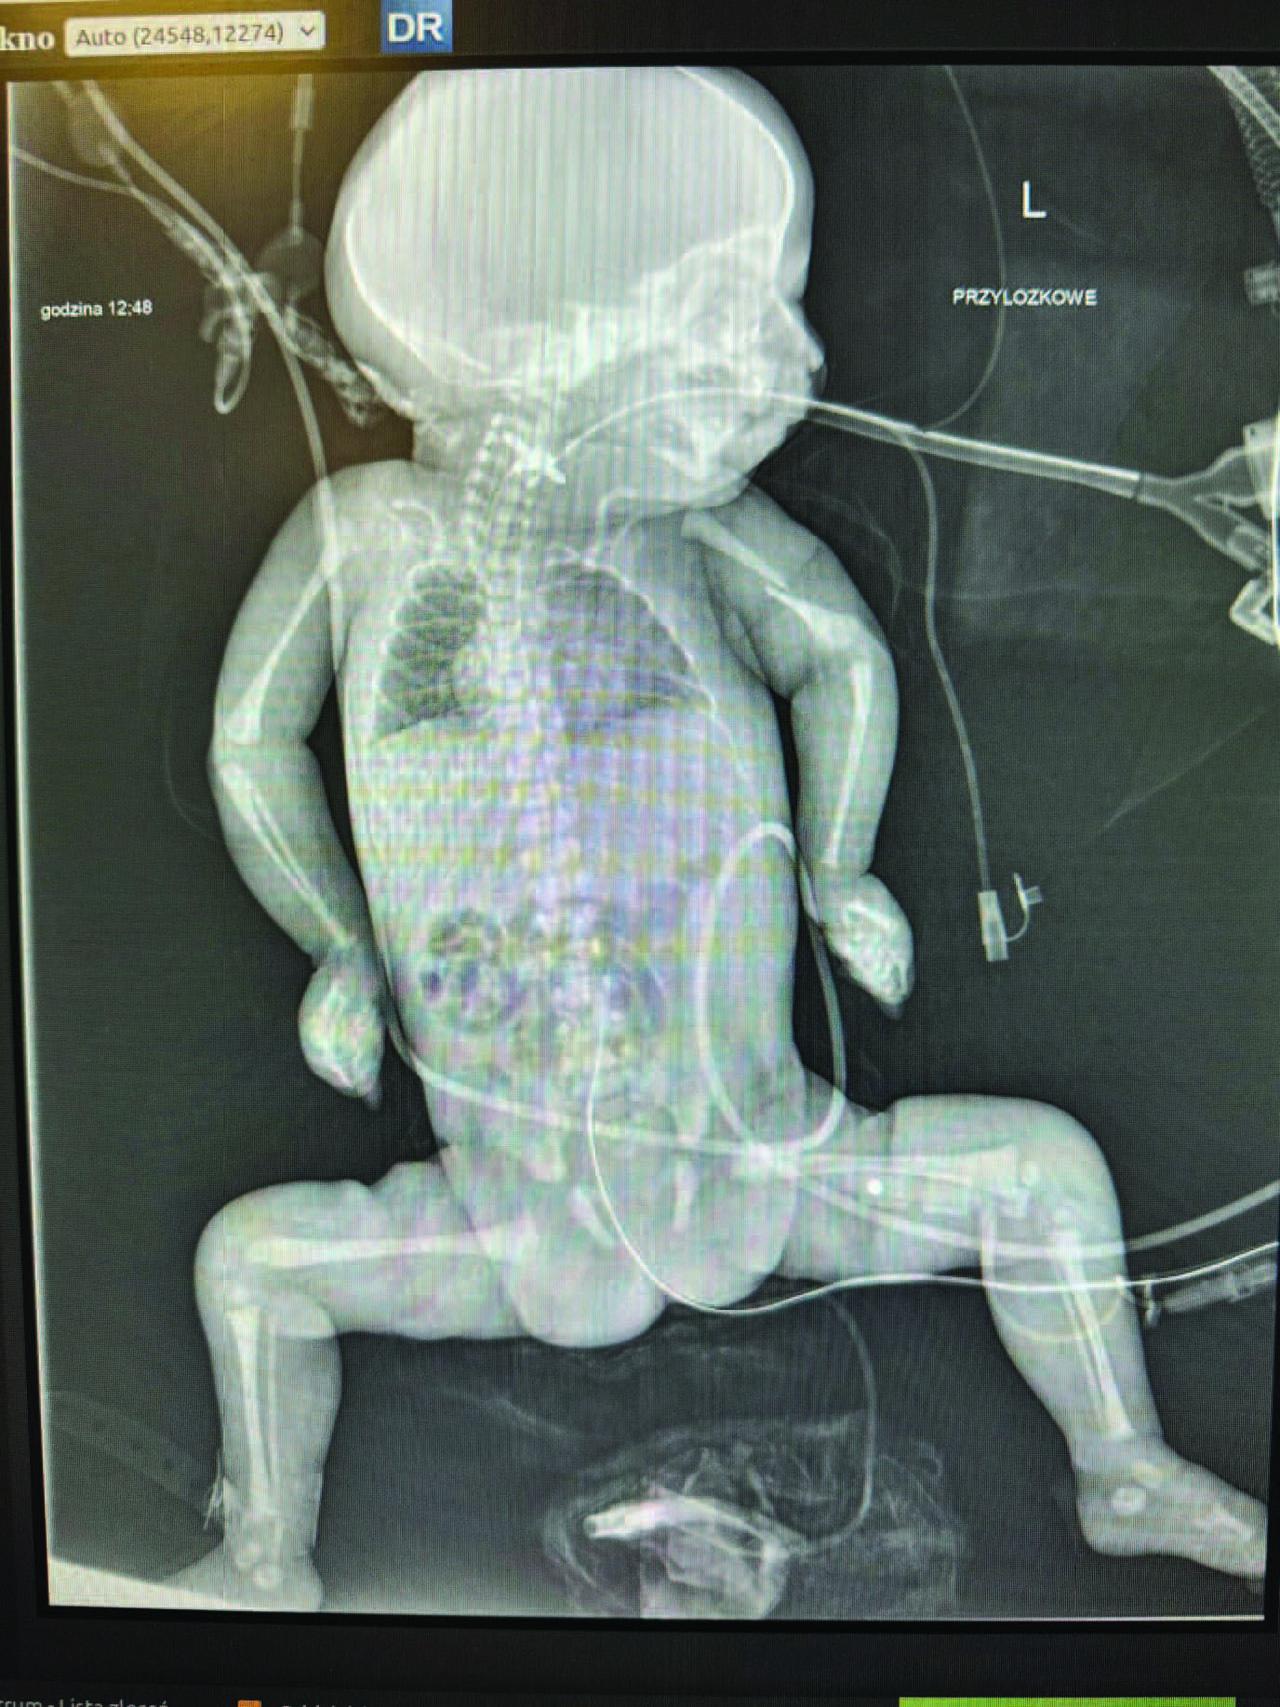

Figure 1.